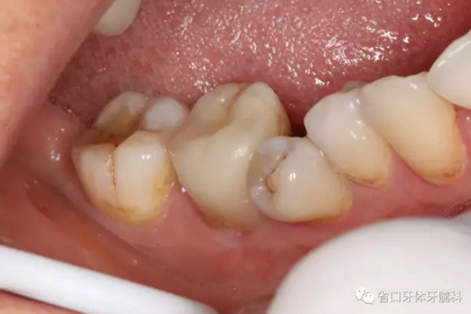

處置:46/清理髓腔,自酸蝕粘接,流動樹脂覆蓋根管口,牙體預(yù)備

圖3 牙體預(yù)備后,近中頰側(cè)牙體缺損平齊齦緣;近頰根管口流動樹脂覆蓋牙膠不足,下次改進(jìn)

圖4 牙體預(yù)備后頰側(cè)觀